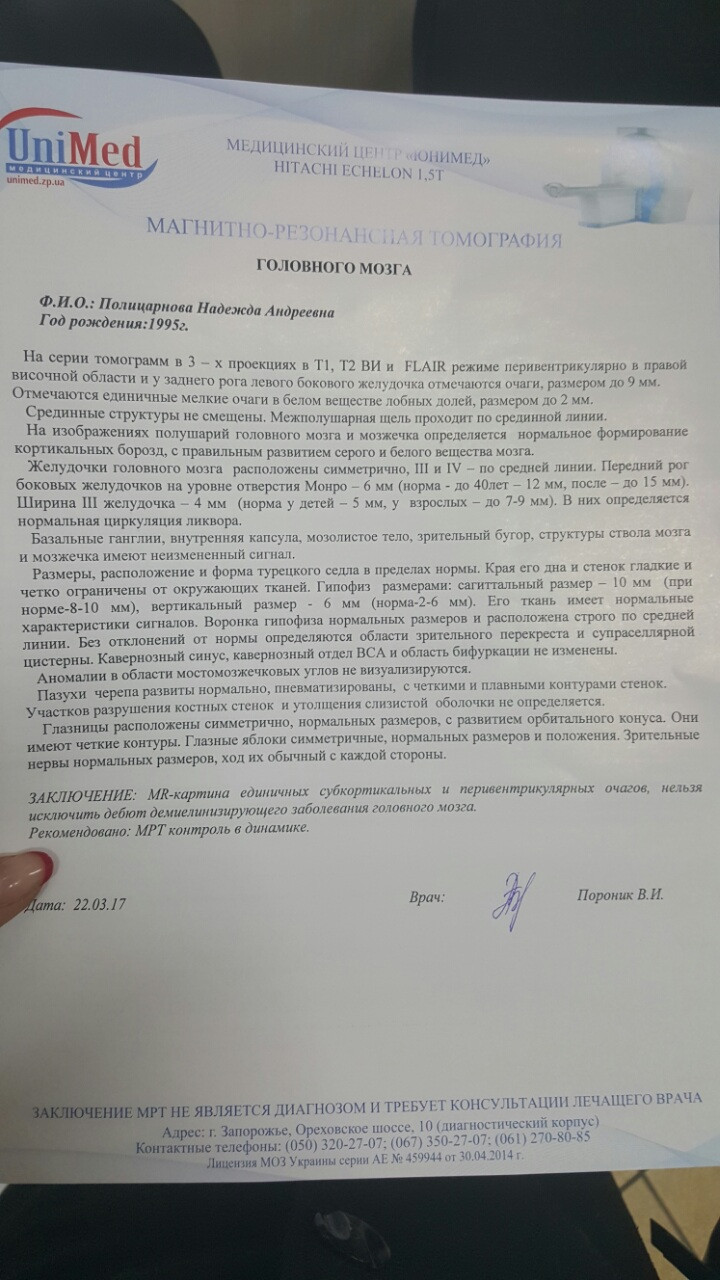

МРТ головного мозга: Расшифровка снимков и Интерпретация

Раздел: Визуальные уроки